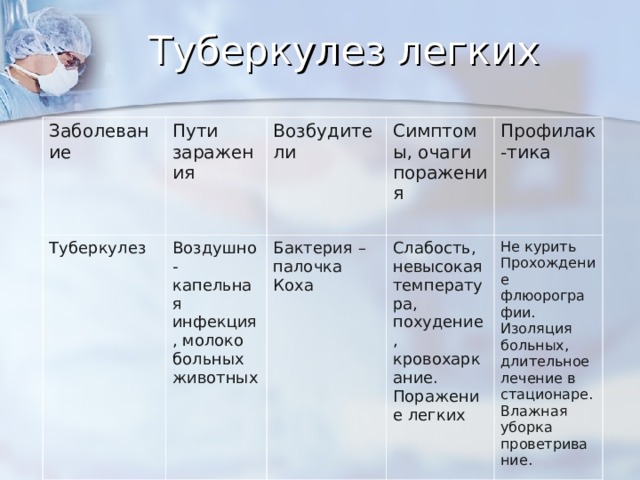

Симптомы туберкулеза: Как распознать и что делать

Раздел: Визуальные уроки